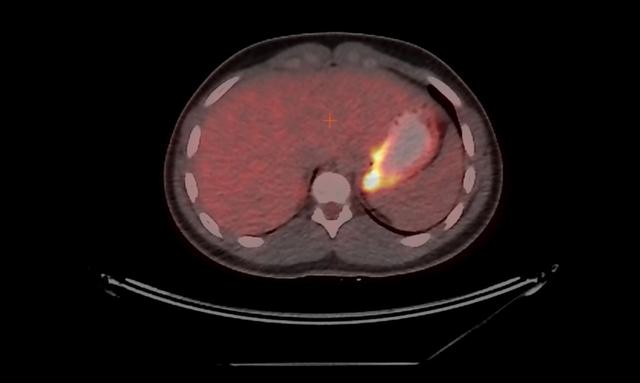

但是,如果只做PET的话,产生的图像的分辨率是非常低的。所以,它经常会结合其他技术(例如CT),来更好地显示一些器官的确切位置。所以,这两者结合我们就可以定位新陈代谢的确切位置,并以亮度来区别新陈代谢的强度。一般来说,癌细胞需要更多的糖,这会导致某些部位出现异常的亮度。所以,PET非常适合早期癌症的发现。